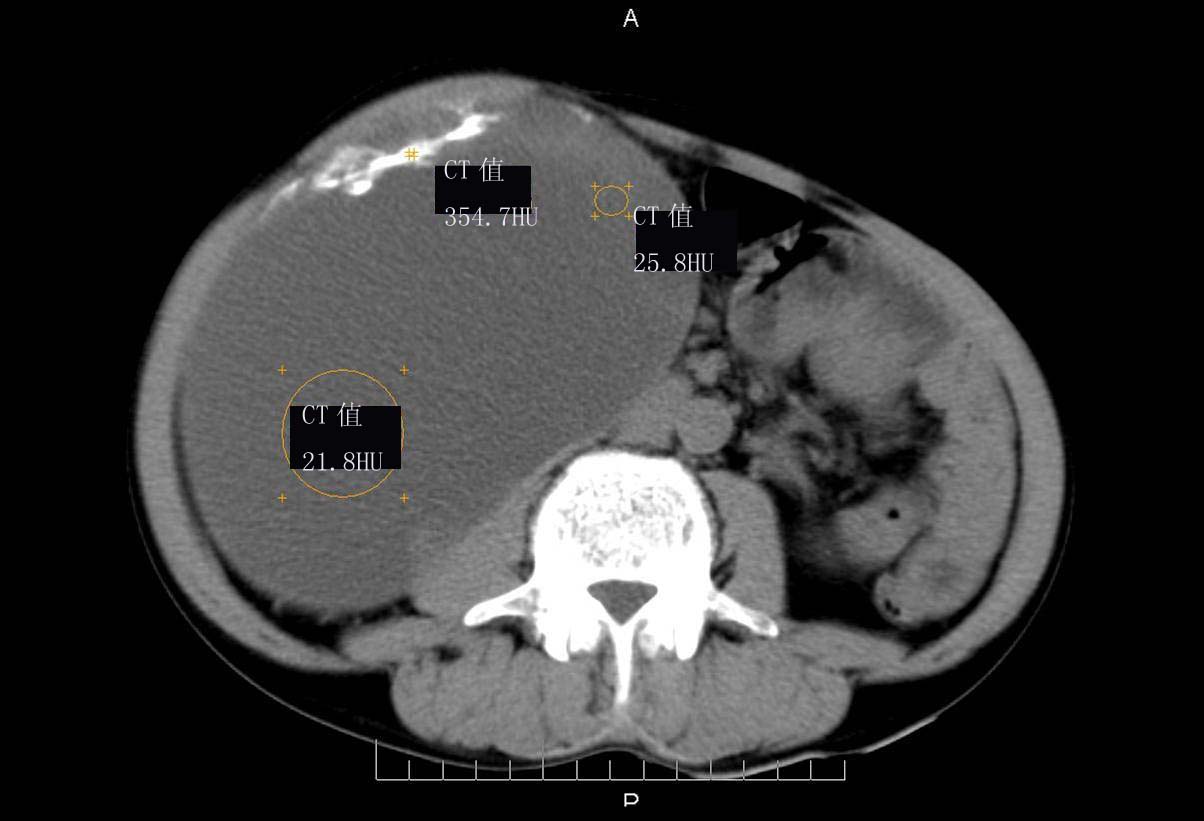

ct值测量

右肾脏巨大囊样影、囊壁有钙化,囊样影轻度强化有软组织成份。不除外畸胎瘤可能。

巨大囊性肿块,囊壁较厚有强化,有团片状钙化,病灶内下方灶内见片絮状高密度影,增强有轻中度强化,考虑囊性肾癌可能性大

右肾上部巨大的囊实性影,实性部分轻度强化。壁有钙化。考虑右肾囊腺癌。右肾盂积水。

定位;肾明显与病灶杯口相交,可以肯定病变来自右肾。

定性;病灶囊性为主,前下部含实性成分,及钙化,部分壁厚薄不均。

肾囊实性病变有;1,囊性肾癌2,囊性肾瘤。3,复杂囊肿。4,重复肾伴积水。然2、3壁相对规则。

综上考虑;囊性肾癌》重复肾伴积水。